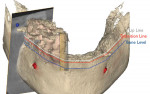

After all the layers were merged by the planning center, the clinician could perform bone contouring and implant planning. For the maxilla, to hide the transition zone, bone needed to be reduced in height. As depicted in Figure 9 through Figure 11, reduction of bone height in the area of tooth No. 8 would enhance implant placement as this would also increase bone width. The blue line in Figure 11 indicates bone level was around 13 mm from the incisal edge of tooth No. 8. For the mandible, to hide the transition zone, the bone needed to be reduced to approximately 18 mm from the incisal edge of tooth No. 27 (Figure 12 through Figure 14). The maxillary and mandibular All-on-4® implant rehabilitation was enabled via adequate restorative space in this patient (Figure 12 through Figure 14) and would replace the missing hard and soft tissues and hide the transition zone behind the lips.15-17